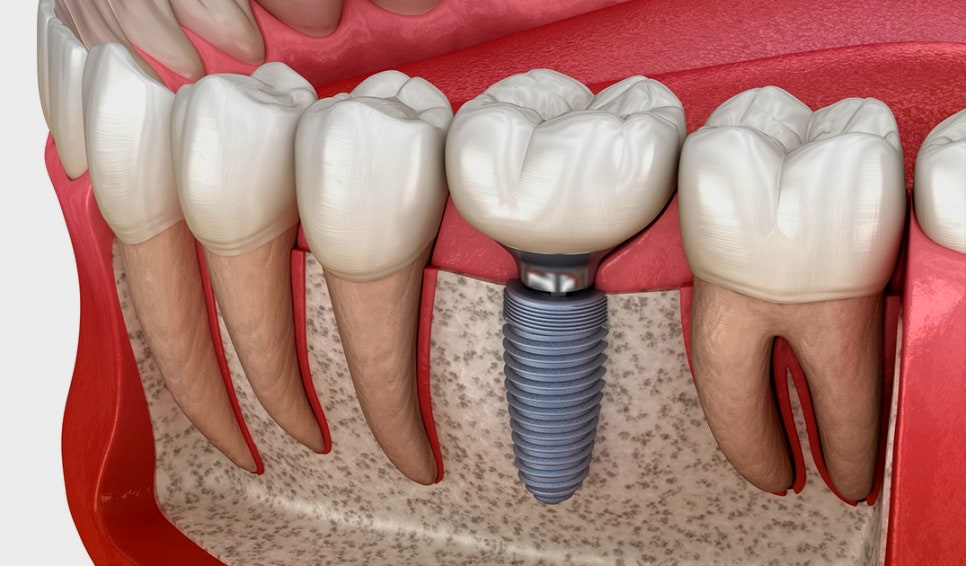

먼저 임플란트는 위와 같이

자연치와 유사한 모습으로

치조골에 고착되어 있는데요

임플란트 는 보통 위와 같이

3가지의 구조로 이뤄지는데요

crown

abutment

fixture

이 세 가지 구조 중에서

초기 고정력을 판단할 수 있는 요소는

fixture 가 뼈에 고착되는 강도입니다.